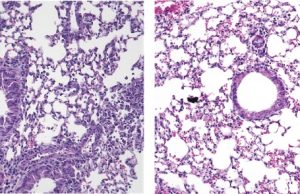

Asma allergica: un nuovo approccio per ridurre l’infiammazione polmonare

I ricercatori della Keck School of Medicine, University of Southern California, hanno scoperto che una proteina chiamata Piezo1 impedisce a un tipo di cellula...